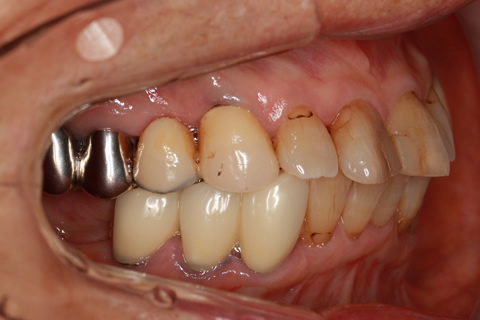

オールセラミックの症例6

40年前の金歯をジルコニアセラミックスで治療。

- 年齢・性別

- 65歳男性

- 治療期間

- 1ヶ月

- 抜歯

- なし

- 治療費

- 8.8万円

- 備考

- 金歯をセラミックス冠に変更。

- 治療内容

- 歯質を削除し、セラミック冠をセメント合着

- 施術の副作用(リスク)

- 知覚過敏、歯髄炎、荷重負担